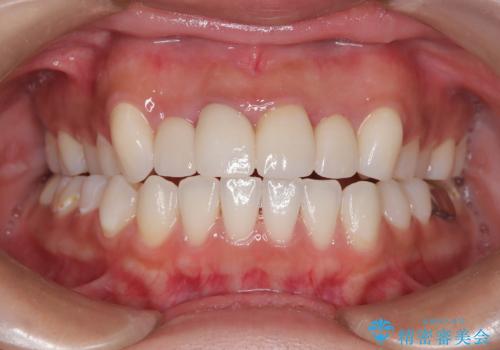

歯周組織がある程度改善されるまでに3か月ほどかかりました。

いざ型どりしていくというタイミングで、前歯の大きさが違いすぎるのが気になるとのことで歯周外科治療(アピカリ)にて歯肉のラインを整えることに。

歯肉の治りを待ったうえで(約8か月)、最終補綴することとなりました。

補綴はスペシャルです。

結果的に期間がかなりかかってしまいましたが、患者様に満足していただける結果となりました。